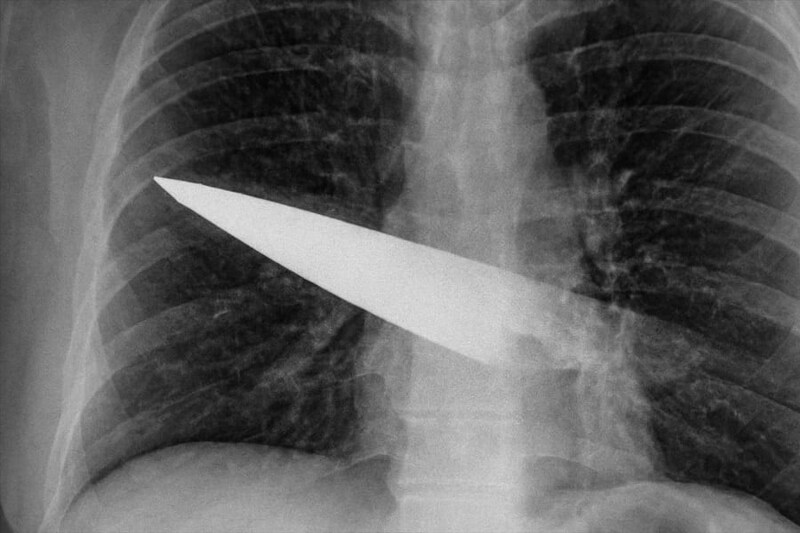

その後、病院でX線検査を受けて初めて、右胸の奥深くに金属製のナイフの刃が残っていることが判明したのです。

こちらは胸部にナイフが刺さっていることを示すX線画像。

さらにCTスキャンでは、刃は背中の第5・6肋骨の間から体内に入り、胸の前面(第3・4肋骨の間)まで貫通していることが分かりました。